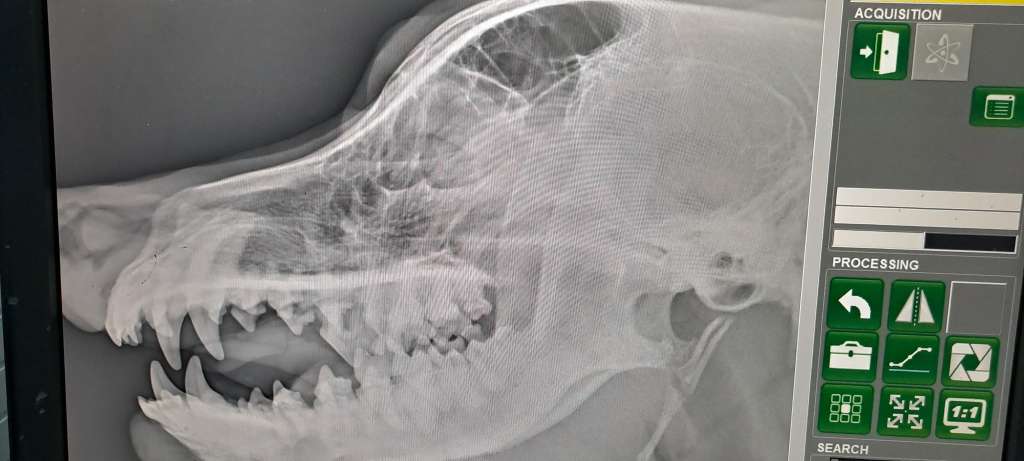

Discovering that your dog has a tumor is a devastating moment for any pet owner. In Arya’s case, the journey to a correct diagnosis was filled with confusion, delays, and emotional struggle. Here, I want to share the full story of how we went from a strange swelling under the tongue to a confirmed case of fibrosarcoma in the jaw.

The Shock During Surgery

While attempting to remove the mass, the surgeon discovered something unexpected and deeply concerning:

“The tumor is stuck to the jawbone. I can’t fully remove it without damaging the jaw.”

The Diagnosis: Oral Fibrosarcoma in the Lower Jaw

After several anxious days waiting for the lab results, the surgeon confirmed it:

“Your dog has oral fibrosarcoma attached to her lower jawbone.”